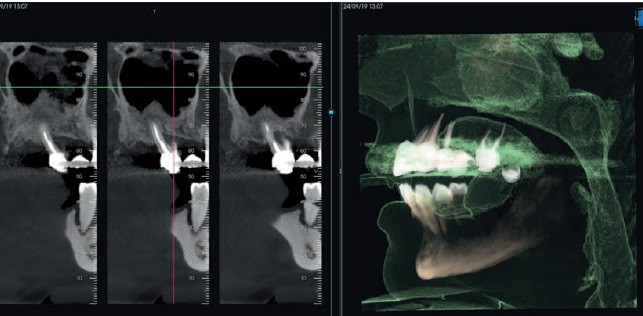

CORE 1000 biedt een breed scala aan volumetrische groottes, elk ontworpen voor specifieke behoeften. Met speciale FOV's, filters, geoptimaliseerde protocollen en Scout View halen gebruikers het maximale uit hun apparatuur en genieten van steeds betere prestaties.

Met de zeer flexibele geavanceerde oplossingen van CORE kan men zelfs de de meest complexe morfologieën onderzoeken, zelfs de kleinste anatomische details vastleggen en mogelijke positioneringsfouten van de patiënt corrigeren.